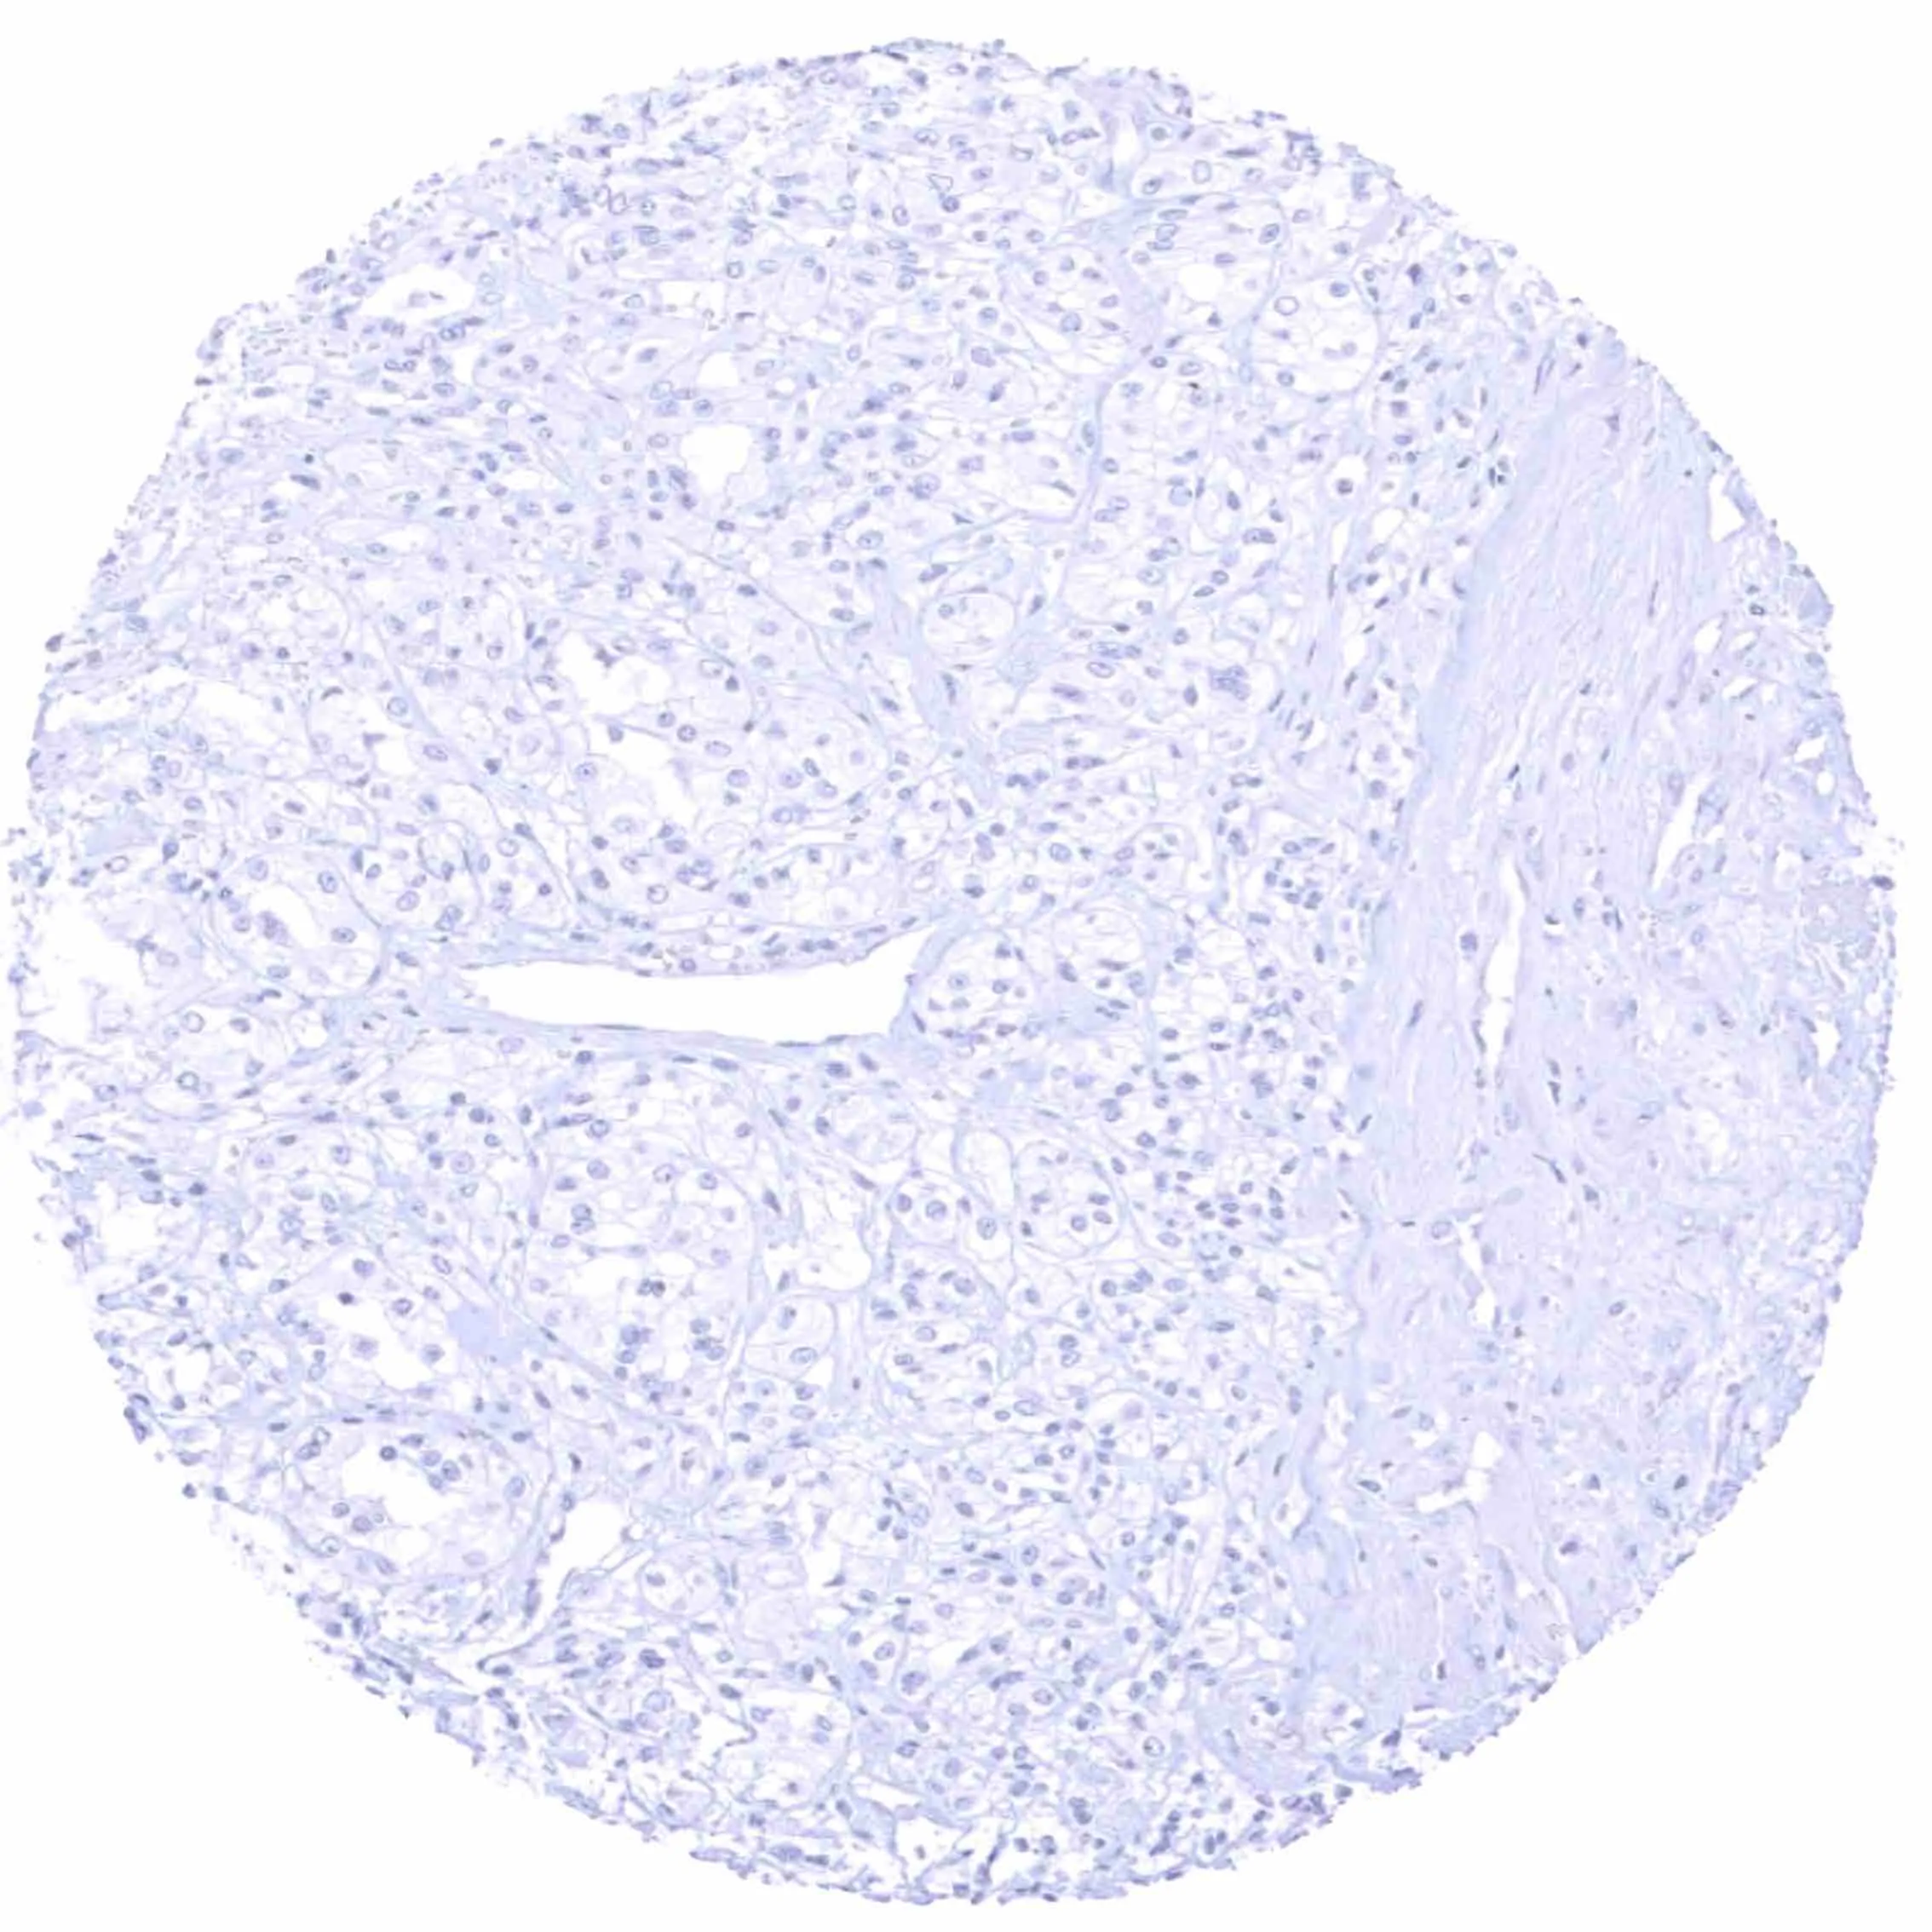

Kidney – EGFRvIII negative clear cell carcinoma.

Kidney – EGFRvIII negative oncocytoma.

Kidney – EGFRvIII negative papillary renal cell carcinoma.